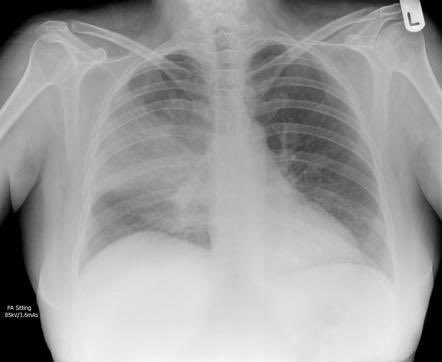

diagnosed through a physical examination, chest x-ray, and blood tests. A chest x-ray can show inflammation and fluid in the lungs, while blood tests can help identify the type of pathogen causing the infection. In some cases, other tests such as a sputum culture or bronchoscopy.